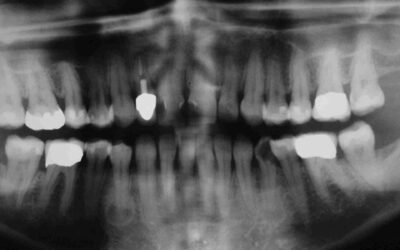

Solche umfassenden Rehabilitationen kann man, wenn man ruhig schlafen will, nur eingliedern, wenn man sich praktisch 100%ig auf seine Endodontie verlassen kann (Timbuktu-Methode)

....nicht an die noch heute geltende Lehrmeinung gehalten, man dürfe Zähne nicht verblocken. Zwischenzeitliche zahnärztliche Interventionen regelmäßige Zahnreinigungen mehrere adjustierte Aufbisschienen eine Wurzelbehandlung an 46 ca.10 Jahre nach Überkronung Die...